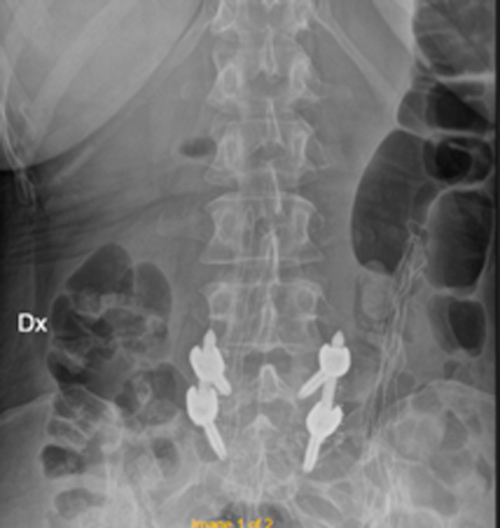

DIAGNOSI:

SPONDILOLISTESI CON STENOINSTABILITA’ L3-L5

Radiografia lombare pre-operatoria

Intervento chirurgico eseguito:

Artrodesi lombare mediante viti transpeducolari L3-L4-L5 + introduzione di cage intersomatica plif

Radiografia post-operatoria